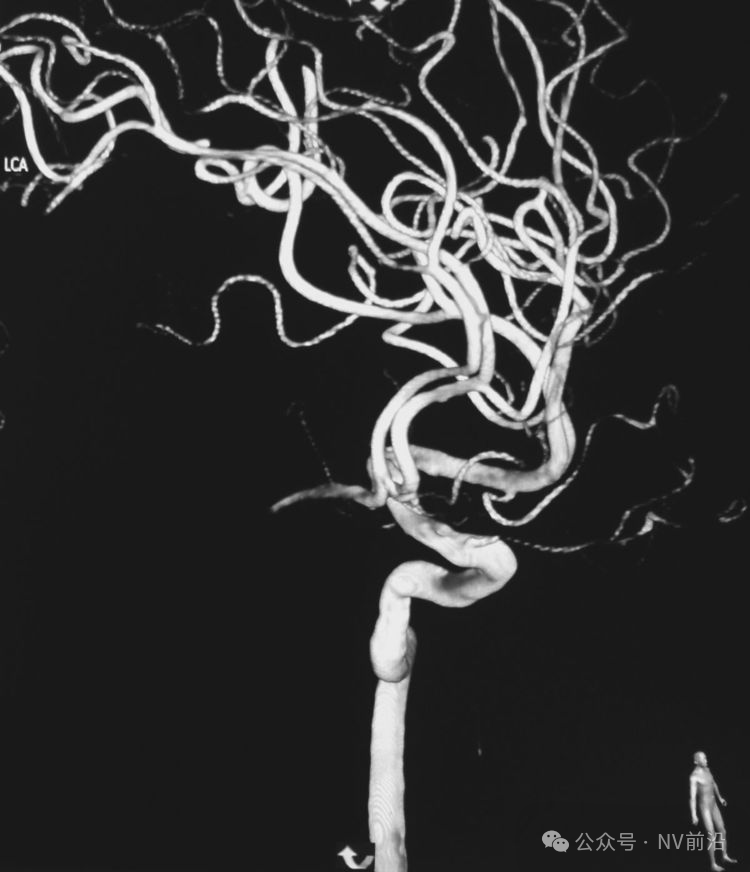

病例一,左侧微小眼动脉瘤,未破裂。

测量:瘤体2.09×2.34 mm,颈宽2.66 mm。

工作位造影

右椎动脉造影三维重建